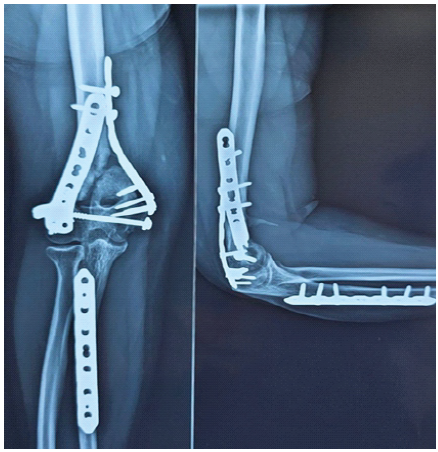

Serial radiographs showed satisfactory alignment and intact fixation of both the distal humerus and ulnar fractures. The ulnar fracture had united, while the distal humerus displayed persistent fracture lines and absence of callus formation consistent with non-union. At 6 months post-operatively, there was no bridging callus, and the fracture ends appeared atrophic (Fig. 3). Hardware remained intact, and no malalignment or implant failure was seen.

Figure 3: Six-month post-operative anteroposterior and lateral radiographs showing persistent distal humerus non-union with visible fracture lines and intact fixation hardware.

Since plain radiographs adequately defined the pathology, a CT scan was considered unnecessary. The diagnosis of aseptic atrophic non-union of the distal humerus was established.